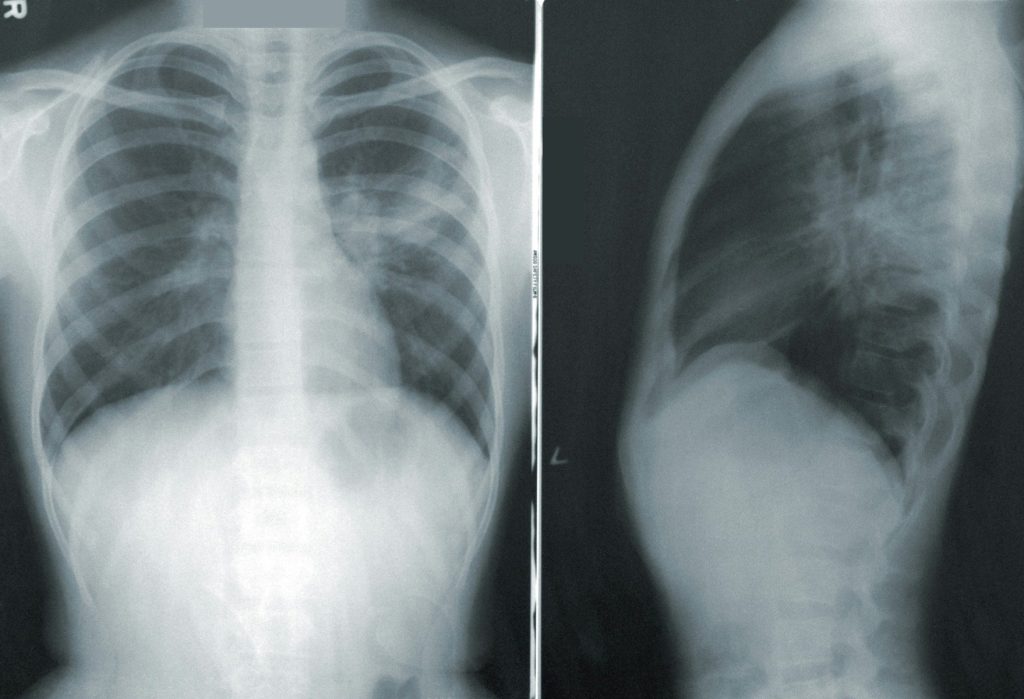

Tuberculoza este o boală prevenibilă și curabilă, cauzată de o bacterie care afectează, cel mai frecvent, plămânii. Aceasta se transmite prin aer, atunci când persoanele infectate tusesc, strănută sau scuipă.